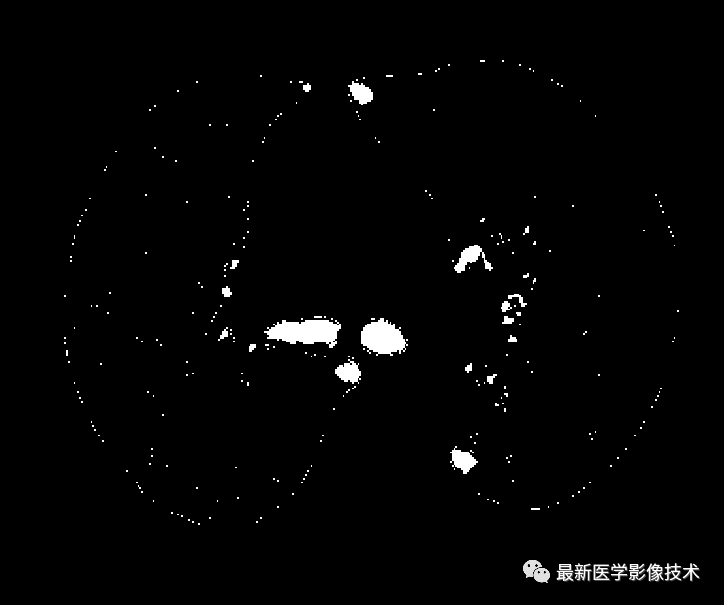

之前文章也说过可以采用Hessian矩阵来增强血管区域,医学图像处理案例(六)——生成血管三维模型所以这里利用Hessian矩阵是多维变量函数的二阶偏导数矩阵,根据其特征值的属性来检测管状类的结构,例如三维Hessian的特征值有lambda_1,lambda_2和lambda_3。 明亮的管状结构有 低的lambda_1和大的lambda_2和lambda_3负值。 相反, 暗管状结构时lambda_1值较低,lambda_2和lambda_3的正值较大。 明亮的板状结构具有较低的lambda_1和lambda_2值以及较大的lambda_3负值。暗的板状结构具有较低的lambda_1和lambda_2值以及较大的lambda_3正值。明亮的球形(斑点)结构具有所有三个特征值都是较大的负数。暗的球形(斑点)结构将具有三个特征值都是较大的正数。所以我们可以通过选择特征值来增强气管区域。 增强后的气管区域还需要阈值分割处理,如下图所示。

四、VESSEL12的肺部气管区域后处理

观察到从上图可以看出气管区域得到了显著增强的同时还需要注意并非所有增强的区域都属于气管因此需要对这些非气管但被增强的区域进行去除处理在此阶段采用最大连通域算法来进行后续处理具体效果如图所示最终能够清晰识别出具有显著特征的气管区域轮廓

最后,我们将该区域与原始图像进行结合,生成肺部气管三维模型结果。